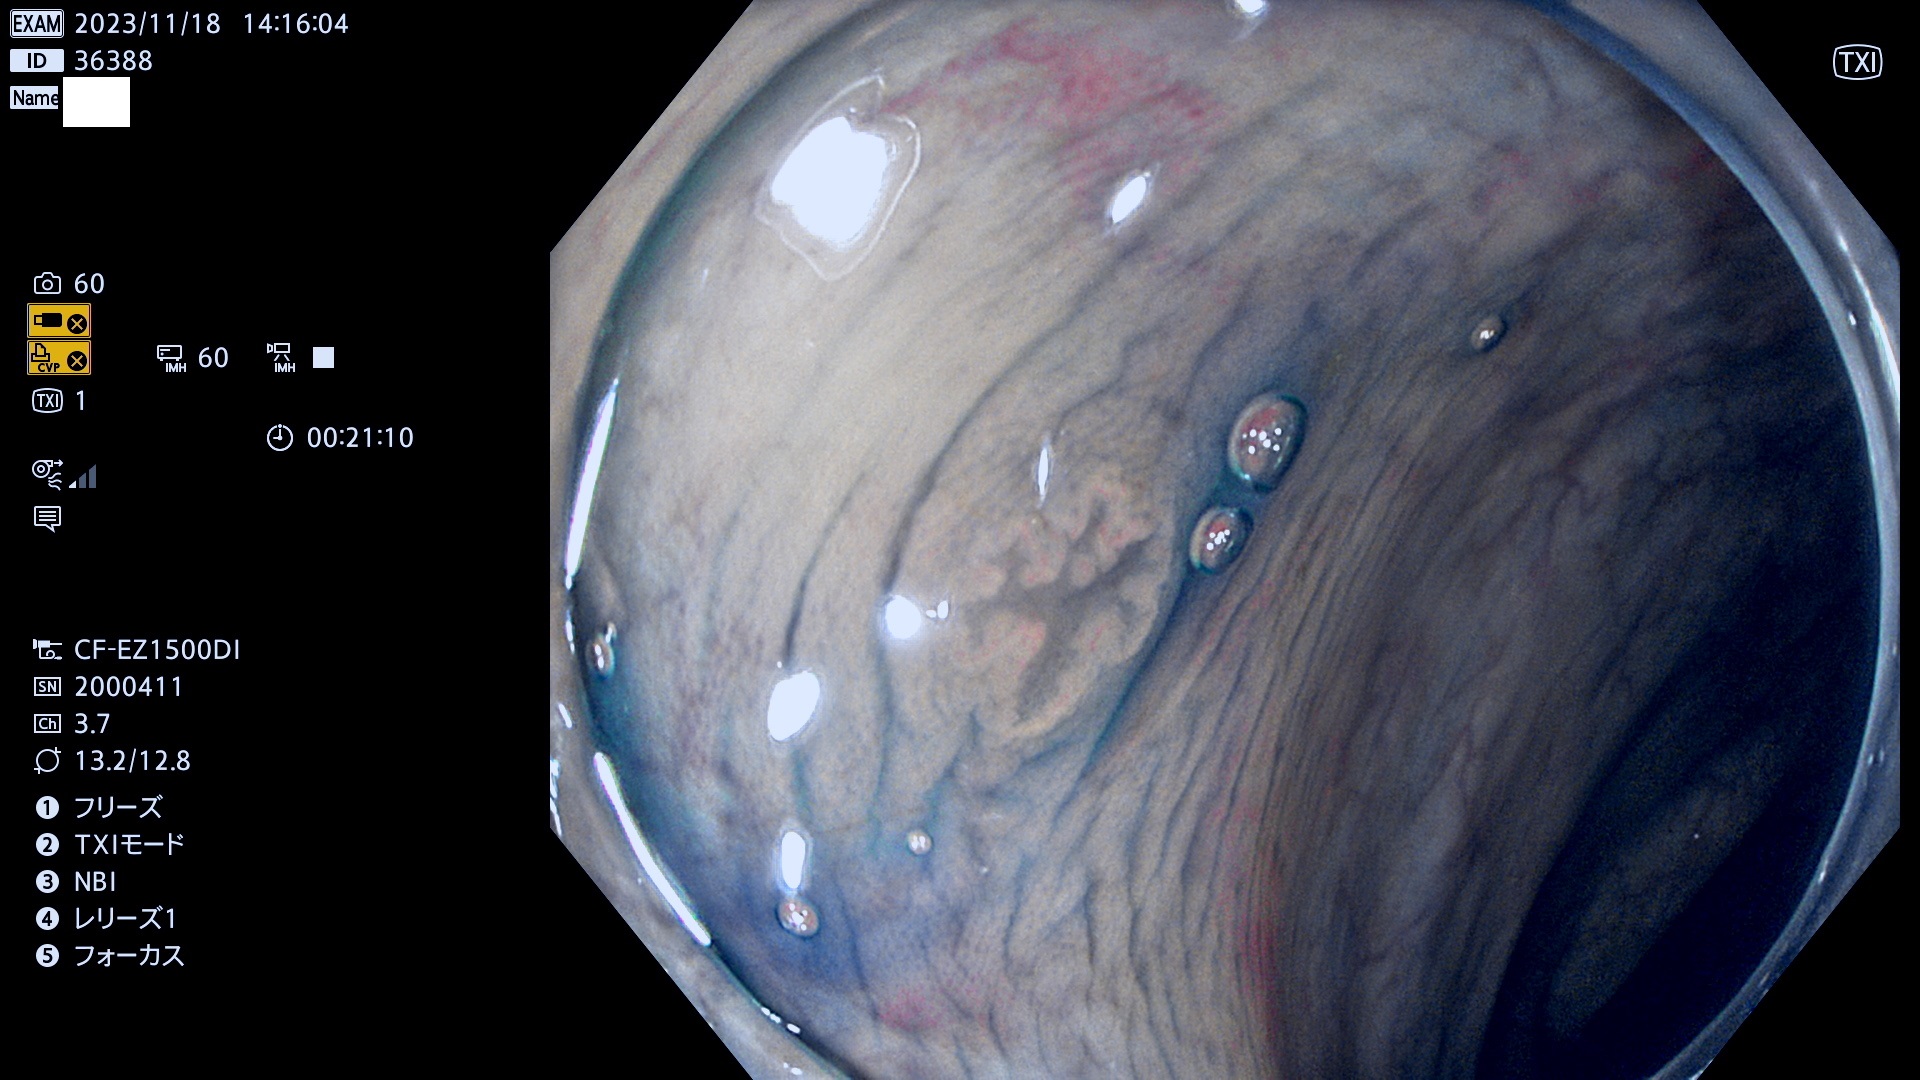

今週のUb、Uc型腺腫

表面型腺腫(Flat Adenoma)の中で、完全に平坦な物をUb、陥凹している物をUcと呼びます。平坦隆起型(Ua)よりも、発見が難しく危険な病変です。このタイプは「内視鏡後・大腸癌の重要犯人」であり、この発見率は「腺腫発見率」よりも、重要な意味があります。

毎週の検査(木・金・土・日)に発見されたUb、Uc型・腺腫を、その週の日曜の夜にUPし1週間、提示します。

抽出の対象期間 2023年11月16日(木)〜11月20(日)の5日間(60件の検査)11件